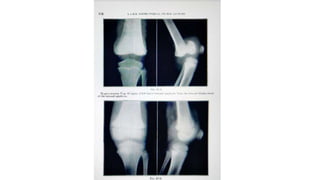

• Fracture of lateral condyle humerus (capitellum ) is type 4 injury

• Weekly x-rays needed to check the alignment

• When it’s displaced , open reduction is must

• Elbow is immobilised for 3 weeks in 90° flexion

• If not reduced properly – may lead to over growth of radial head /

valgus deformity / tardy ulnar nerve palsy

• Fracture oflateral condyle humerus (capitellum ) is type 4 injury • Weekly x-rays needed to check the alignment • When it’s displaced , open reduction is must • Elbow is immobilised for 3 weeks in 90° flexion • If not reduced properly – may lead to over growth of radial head / valgus deformity / tardy ulnar nerve palsy